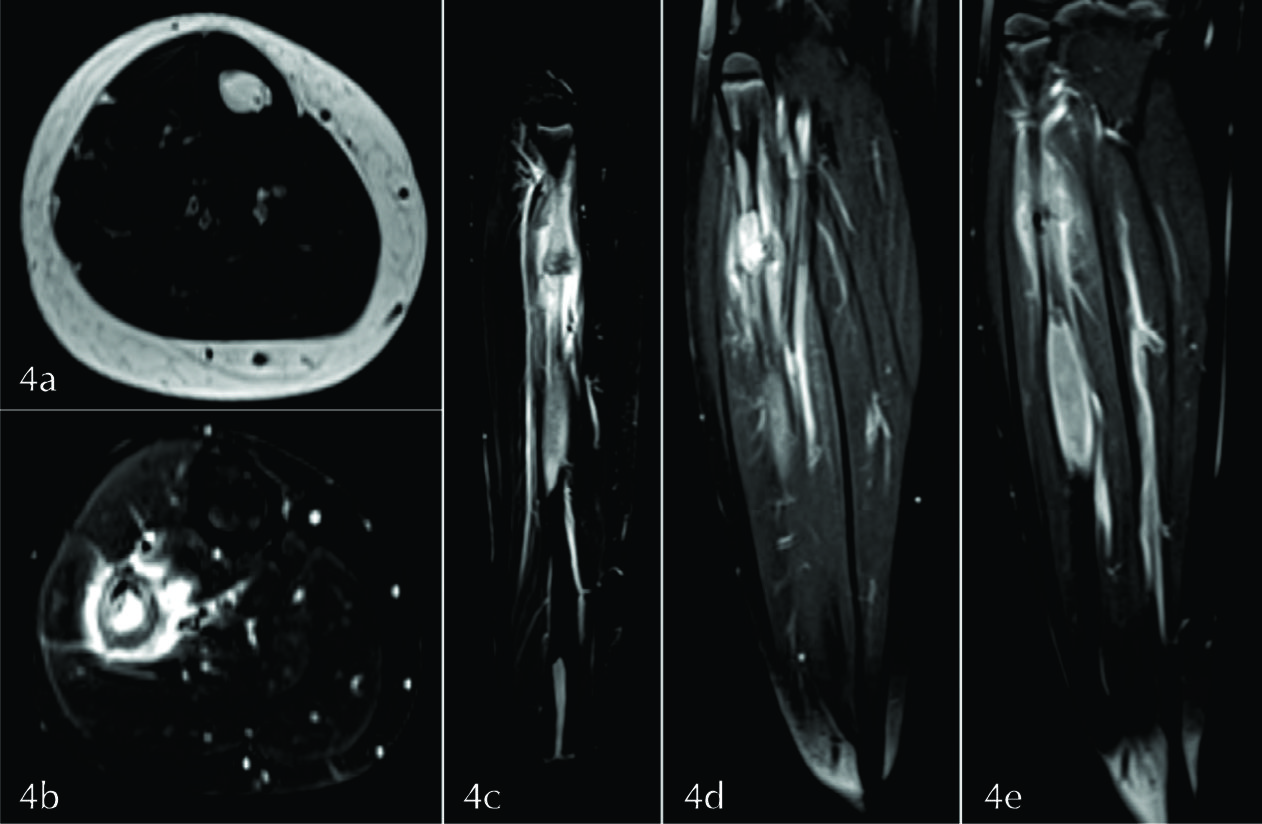

Figura 4

RM de MMII. a) Plano axial potenciado en T1 a nivel de la lesión del tercio medio del peroné, b) DP FAT SAT en el plano axial a nivel de la lesión del tercio superior, c) DP FAT SAT en el plano sagital, d y e) T1 en el plano coronal tras la administración de medio de contraste. Las lesiones son isointensas con el músculo en secuencias potenciadas en T1 (flecha amarilla), hiperintensas en DP con FAT SAT (flechas blancas), presentando realce intenso y homogéneo con el medio de contraste (flechas celestes). En la lesión superior se identifica el trazo de fractura y la reacción perióstica asociada (flecha verde), así como la presencia de edema intra óseo y de partes blandas (flechas naranjas). La lesión del tercio inferior contacta con la fisis (flecha roja).